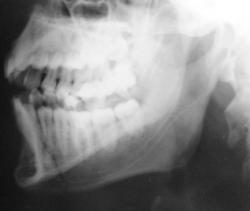

Выяснение "отношений" продолжается.

Ваше мнение коллеги.

на мой взгляд здесь перелом суставного отростка